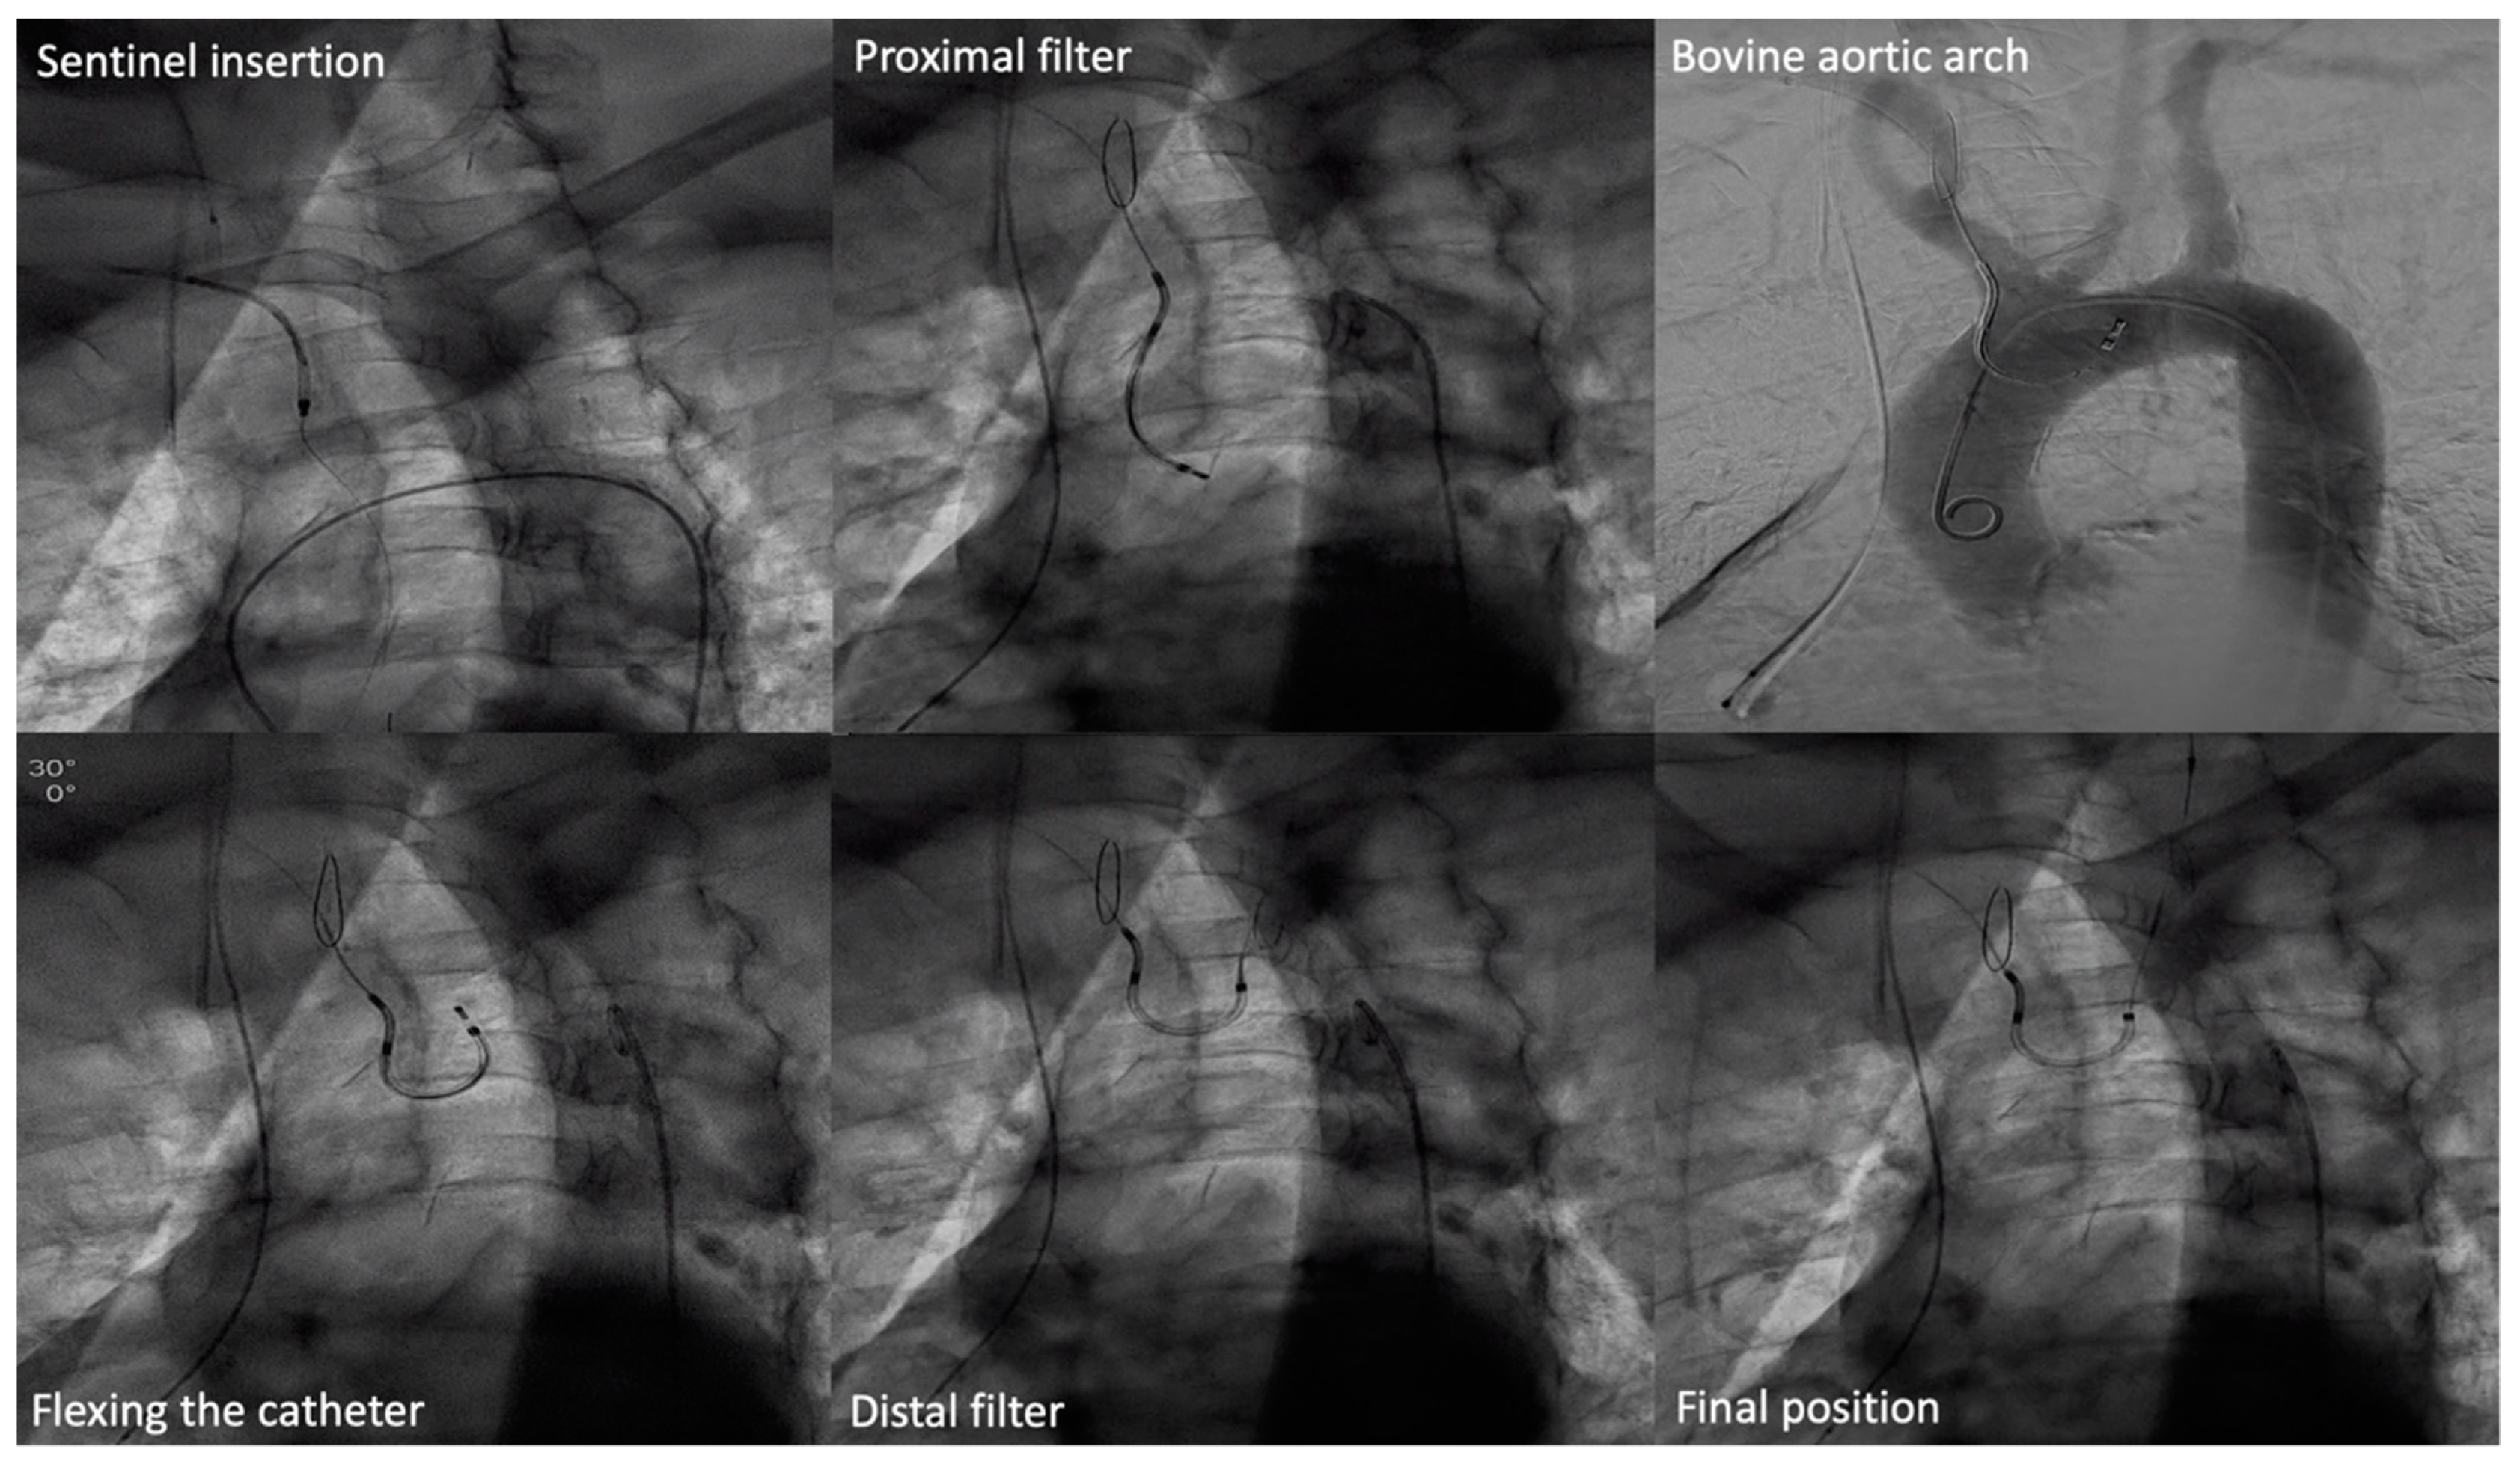

- Rozado, J.; Padron, R.; Alperi, A.; Pascual, I.; Cubero, H.; Ayesta, A.; Avanzas, P.; Moris, C. TAVI Procedures with Sentinel Device in a Bovine Aortic Arch. Neurological Protection during TAVI. In Eapci Textbook of Percutaneous Interventional Cardiovascular Medicine; Part II. PCR.; Piazza, N., Cribier, A., De Palma, R., Eds.; Europa Digital & Publishing: Toulouse, France, 2012. [Google Scholar]